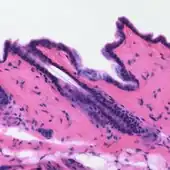

L'hématoxyline, noir de campêche ou noir naturel 1 (C.I. 75290) est un composé organique de formule C16H14O6. C'est un colorant noir, extrait du duramen du campêche (Haematoxylum campechianum)[5],[6]. Il est notamment utilisé en histologie, comme encre[7],[8],[9],[10] et comme teinture dans l'industrie du textile et du cuir [11],[12]. En histologie, la coloration à l'hématoxyline est souvent suivie par une à l'éosine[13],[14],[5] (contre-coloration), ce procédé étant appelé « coloration HE », une des associations de colorants les plus utilisées dans le domaine[5],[15],[16],[11],[17]. L'hématoxyline est aussi un des composants de la coloration de Papanicolaou (coloration PAP) très utilisée en cytologie[17],[5].

L'hématoxyline peut servir seule de colorant histologique. Elle est principalement utilisée pour la coloration des noyaux de cellule, mais elle colore également le réticulum endoplasmique rugueux, les ribosomes, le collagène, la myéline, les fibres élastiques et les mucines acides[13]. L'hématoxyline seule n'est pas un colorant efficace, mais oxydée en hématéine et combinée avec un mordant, elle peut colorer la chromatine d'un noyau d'une teinte allant du bleu foncé au noir[5],[11],[29],[13]. La couleur et la spécificité de la coloration à l'hématoxyline dépendent sa nature chimique, sa quantité, le mordant utilisé, et le pH de la solution colorante ; ainsi, plusieurs formulations à base d'hématoxyline ont été développées[5],[13],[18].

L'hématoxyline est également très souvent associée avec un ou plusieurs autres colorants. L'une des associations les plus utilisées en histologie est celle avec l'éosine[13],[14],[5], on parle alors de coloration HE[5],[15],[11],[17]. L'hématoxyline est également, avec l'éosine et l'orange G, un composant de la coloration de Papanicolaou (coloration PAP) très utilisée en cytologie, notamment pour le test PAP de dépistage du cancer du col utérin[17],[5]. On peut également citer la coloration HPS (en) (hématoxyline/phloxine/safran), la coloration HES (hématoxyline/éosine/safran), la coloration de van Gieson (en) (hématoxyline/fuchsine acide/acide picrique), la coloration de Goldner (hématoxyline/fuchsine acide/RAL 6027), la coloration de Ladewig (orange G/bleu de méthylène/fuchsine acide/hématoxyline) et la coloration PAS (hématoxyline/acide periodique/réactif de Schiff)